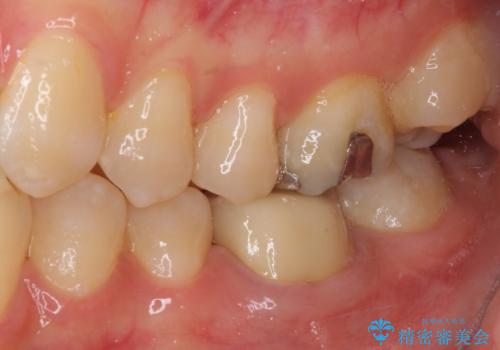

仮歯に置き換えた時点で希望に近い形態とできたので、その形を踏襲してオールセラミッククラウンを製作してもらいました。

気になっていた形が改善され、色調も自然なものとなったので、患者様には大変満足していただきました。